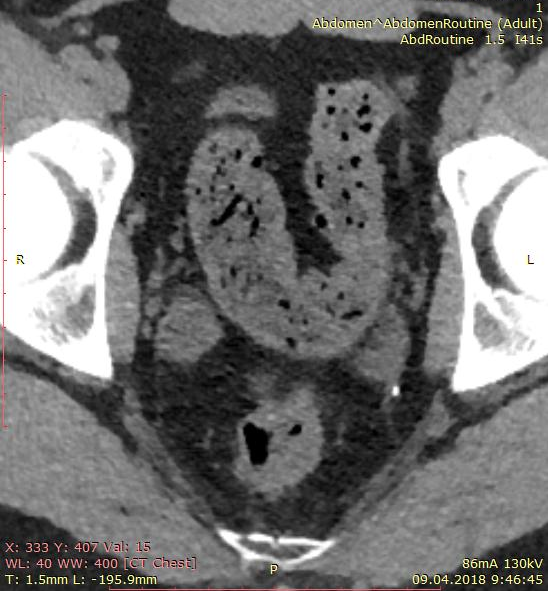

КТ-исследование абсцесса малого таза: Визуализация и диагностика

Раздел: Фотоальбом решений